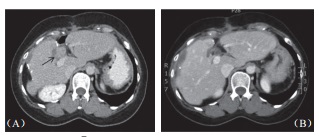

2位出現(xiàn)并發(fā)癥病患均為乙肝患者,肝硬化B級,均有糖尿病病史,均為肝臟手術后復發(fā)病患,腫瘤一在第四段,大小為2.8cm,開腹下以4只探針進行治療,一在第七段,大小為3.2cm,以5只探針進行經(jīng)皮治療。由于并發(fā)癥數(shù)量太少以致難以分析,不過,可見病毒性肝硬化病患,具糖尿病病史,曾經(jīng)手術切除后復發(fā)者,進行開腹式治療,大腫瘤及使用多探針似乎較好發(fā)并發(fā)癥。術后血液分析可見首日低度白血球上升,總膽紅素值上升0.6 mg/dl (0.2~1.3mg/dl),AST 上升90IU/L(45~792IU/L),ALT上升122IU/L(59~875IU/L),alkaline phosphatase上升12IU/L(-2~145IU/L),肌肉酵素creatine kinase上升達140IU/L(12~210IU/L),但96.9%病患均在7日內(nèi)恢復正常。其他術后心電圖變化,腎臟功能指數(shù)或是尿液分析均為正常,一個月內(nèi)影像上未見膽管受損跡(圖2),也無肝臟缺血壞死區(qū)出現(xiàn),但無肝內(nèi)膿瘍出現(xiàn)。

圖2 62 歲男性肝癌病患在接受手術及射頻消融后于總膽管及門脈旁復發(fā),(A)3cm×2.8cm 大小腫瘤(箭頭處)直接貼近肝門;B)消融后6個月腫瘤消失,消融區(qū)縮小明顯,鄰近膽管無擴張